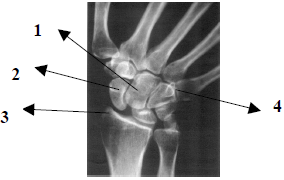

Observe atentamente a imagem radiográfica abaixo e em seguida responda a questão.

Pela anatomia radiológica demonstrada na imagem, podemos afirmar que trata-se da incidência

A

PA de pé.

B

PA de mão.

C

PA de punho.

D

PA de punho com desvio ulnar.